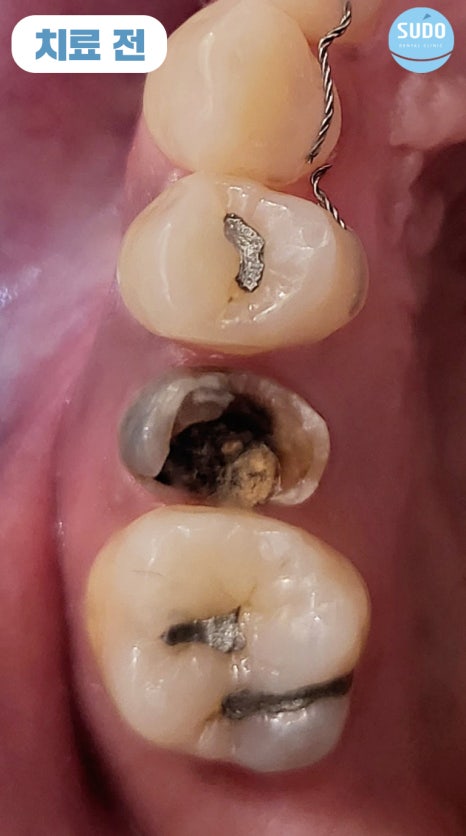

위 환자분은 30대 초반 여성분으로, 고등학생일 때 치료 받았던 금니가 빠져 저희 수도치과에 내원해 주셨습니다.

그 부분만을 확대하여 x-ray 사진 촬영해 본 결과 치아 뿌리 안쪽까지 심한 충치로 인해 발치 후 임플란트를 진행하셔야 하는 상태였습니다. 임플란트 경험이 없으셨던 환자분을 위해 수도치과 의료진들의 충분한 치료 설명을 통해 발치 후 부산영도임플란트 식립 계획을 수립하였습니다.

처음 내원하셨을 때는 외국 거주 중이셨고, 열흘 후에 출국 예정이셨습니다. 이에 따라 내원 당일에 발치 후 즉시 임플란트를 식립하셨고, 주변 치아의 이동을 예방하기 위해 유지 철사를 부착한 후 다시 출국하셨습니다.